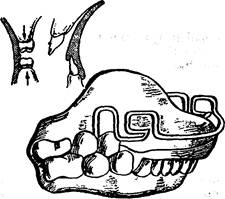

Внутриротовые несъемные аппараты. Дуга Энгля является несъемным аппаратом. Известны две ее разновидности — стационарная и скользящая. Стационарная дуга изготавливается фабрично. Она состоит из отрезка стальной нержавеющей проволоки с резьбой на концах, гаек, навинчивающихся на резьбу, и трубок. К коронкам, изготовленным индивидуально, припаивают трубки скошенными концами назад, чтобы не травмировать слизистую оболочку щек, и параллельно между собой, чтобы можно было ввести в них дугу. Дугу подвязывают лигатурой к зубам (рис. 13.43).

С помощью дуги Энгля этой конструкции можно расширить, удлинить зубной ряд, а также использовать ее как опору для зубоальвео-лярного удлинения.

Для расширения зубного ряда дугу Энгля изгибают шире зубного

ряда, затем концы дуги под напряжением вводят в трубки. Дуга «стремится» возвратиться в первоначальное положение и увлекает за собой все зубы, которые подвязаны к ней лигатурной проволокой. Для удлинения зубного ряда необходимо передние зубы подвязать лигатурой к дуге и при активации гаек, расположенных перед трубками, припаянными к кольцам и коронкам, дуга увеличивается и перемещает за собой передние зубы. Можно перемещать эти зубы и таким способом: дугу изгибают так, чтобы она несколько отступала от перемещаемых зубов; при активации лигатур зубы будут перемещаться в сторону дуги.

Скользящую дугу Энгля применяют при наличии протрузии передних зубов и трем между ними. С помощью этого аппарата можно провести уплощение переднего участка верхнего зубного ряда. Дуга представляет собой отрезок стальной нержавеющей проволоки, концы которой свободно перемещаются в трубках, что связано с отсутствием гаек. Действующей силой являются резиновые кольца. К дуге припаяны зацепные крючки. Между зацепными крючками, припаянными к дуге на уровне первых премоляров, и трубками справа и слева натянуты резиновые кольца. Чтобы дуга не соскальзывала, к десне в переднем отделе припаивают ленточные перекидные кламмеры (рис. 13.44).

Дуги Энгля можно использовать для наложения межчелюстной резиновой тяги между зубными ряда-

Рис. 13.44. Скользящая дуга Энгля.

ми. Ее применяют для смещения нижней челюсти вперед или назад. Одновременно зубной ряд и альвеолярный отросток верхней челюсти испытывают нагрузку в противоположных направлениях (рис. 13.45).